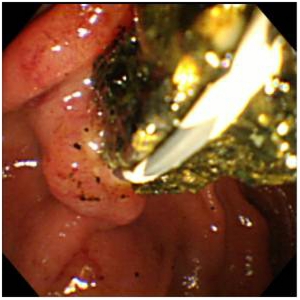

結石が胆管を閉塞し、胆管炎、閉塞性黄疸、急性膵炎などを発症します。緊急の処置が必要な場合が多く、放置すると命に係わる場合があります。通常バスケットカテーテルを用いて、結石を取り除きますが、石が大きい場合はESWL(体外衝撃波結石破砕術)を併用し排石する場合もあります。

ESWLとEST後large balloonによる乳頭拡張術を併用し完全排石に成功した巨大総胆管結石の一例